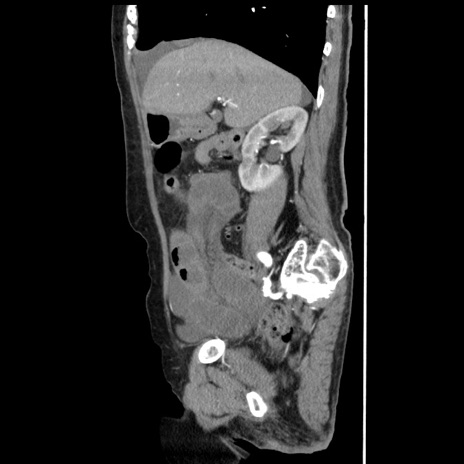

症例1(矢状断像)

【症例】80歳代女性

【主訴】腹痛

【現病歴】8時間前から腹痛あり来院。

【既往歴】糖尿病、脂質異常症、子宮体癌にて子宮全摘術

【身体所見】意識清明・会話良好だが腹痛で苦悶様、全腹部にわたって反跳痛と圧痛あり

【データ】WBC 13600、CRP 0.14、LDH 224、CK 90